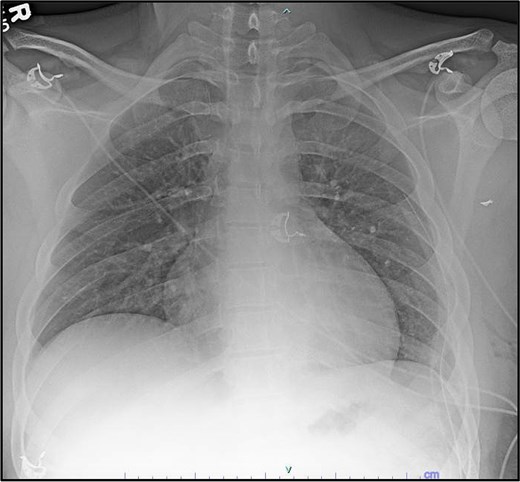

All ports were placed and insufflation was restarted. The robot was docked and instruments were placed. The left arm (Port #1) used a tip-up grasper and the right arm (Port #3) used a long bipolar dissector. The 5 mm mediastinal defect was inspected; the phrenic nerve was directly posterior to the injury. The mediastinal pleura was opened longitudinally above and below the defect (Fig. 4a). A small amount of turbid fluid was evacuated, and the metal foreign body was identified (Fig. 4a and b). With gentle manipulation, the foreign body was rotated, indicating it was not lodged in a structure (Fig. 4c). There was no bleeding to indicate vascular injury. The foreign body (Fig. 4d and e) was grasped and removed in its entirety without damage to surrounding structures. The mediastinal defect was hemostatic and no further dissection was performed. A posterior intercostal nerve block was performed on the intercostal spaces 4–11, and cryoablation of the intercostal nerves level 5–11. The instruments, camera, and sponge were removed, and the robot was undocked. A 24Fr chest tube was placed, the lung was inflated, the chest was closed, and the patient was extubated. The estimated blood loss was 10 ml. The operative time was 1 hour 38 minutes. The foreign body (Fig. 5) was sent to the appropriate authorities.

Incision of the mediastinal pleura (a), initial visualization of the bullet (b), dissection of the pleura (c), removal of the bullet (d), and confirmation of no bleeding with the bullet removed (e).